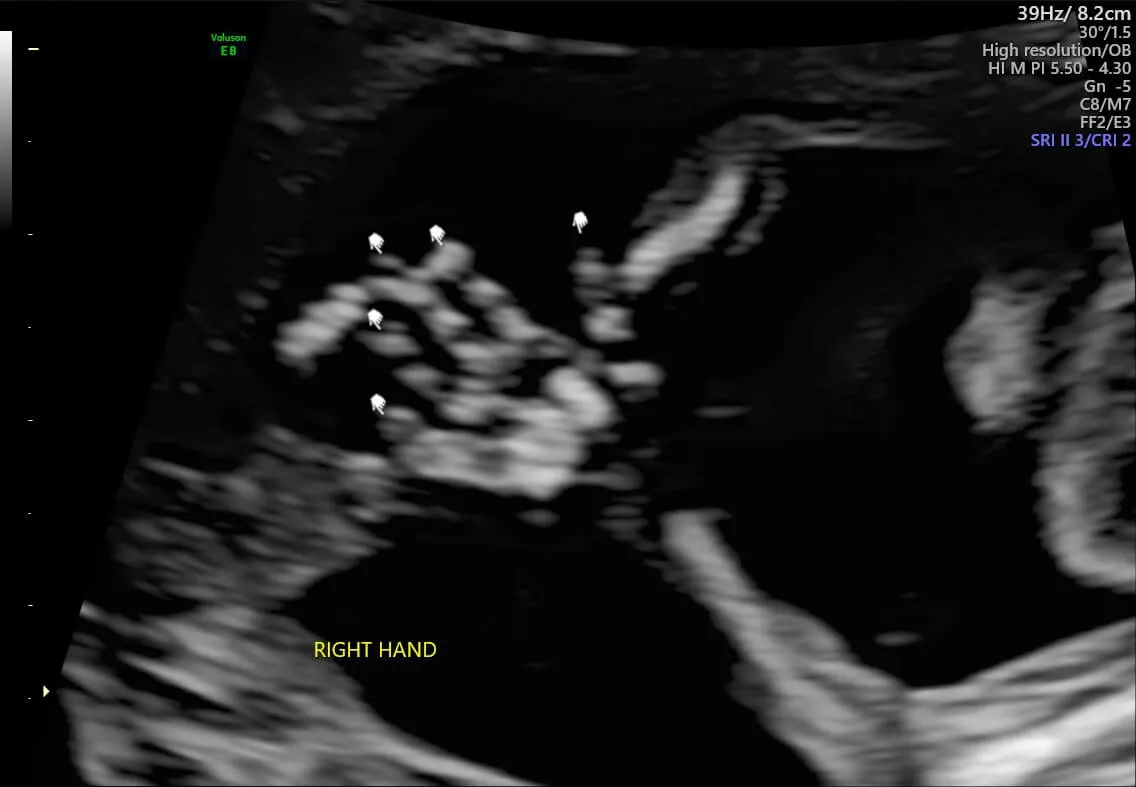

再到四肢、五官清晰可见,能在肚子里动来动去、打嗝、做体操。几个月来,我几乎无时无刻不在感叹和敬畏生命的神奇,碳基生命扳回一局!